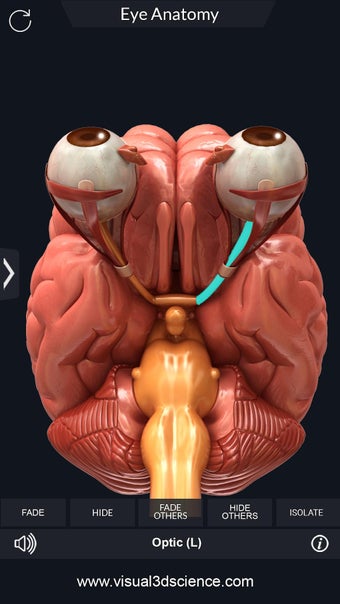

Изучите в деталях человеческий глаз и его анатомию с помощью этого простого в использовании бесплатного приложения для Android. Он позволяет масштабировать и вращать на 360° вокруг высокореалистичной 3D-модели глаза, а также рисовать на экране или прослушивать звуковое произношение каждого термина.

Вы можете выбрать X- просмотр луча, скрытие и отображение отдельных частей глаза, а также рисование или белый цвет на экране и обмен снимками экрана, звуковое произношение для всех анатомических терминов и многое другое.

Каждая часть разделена на отдельный вид, где вы можете можно увидеть название детали и ее расположение на глаз.